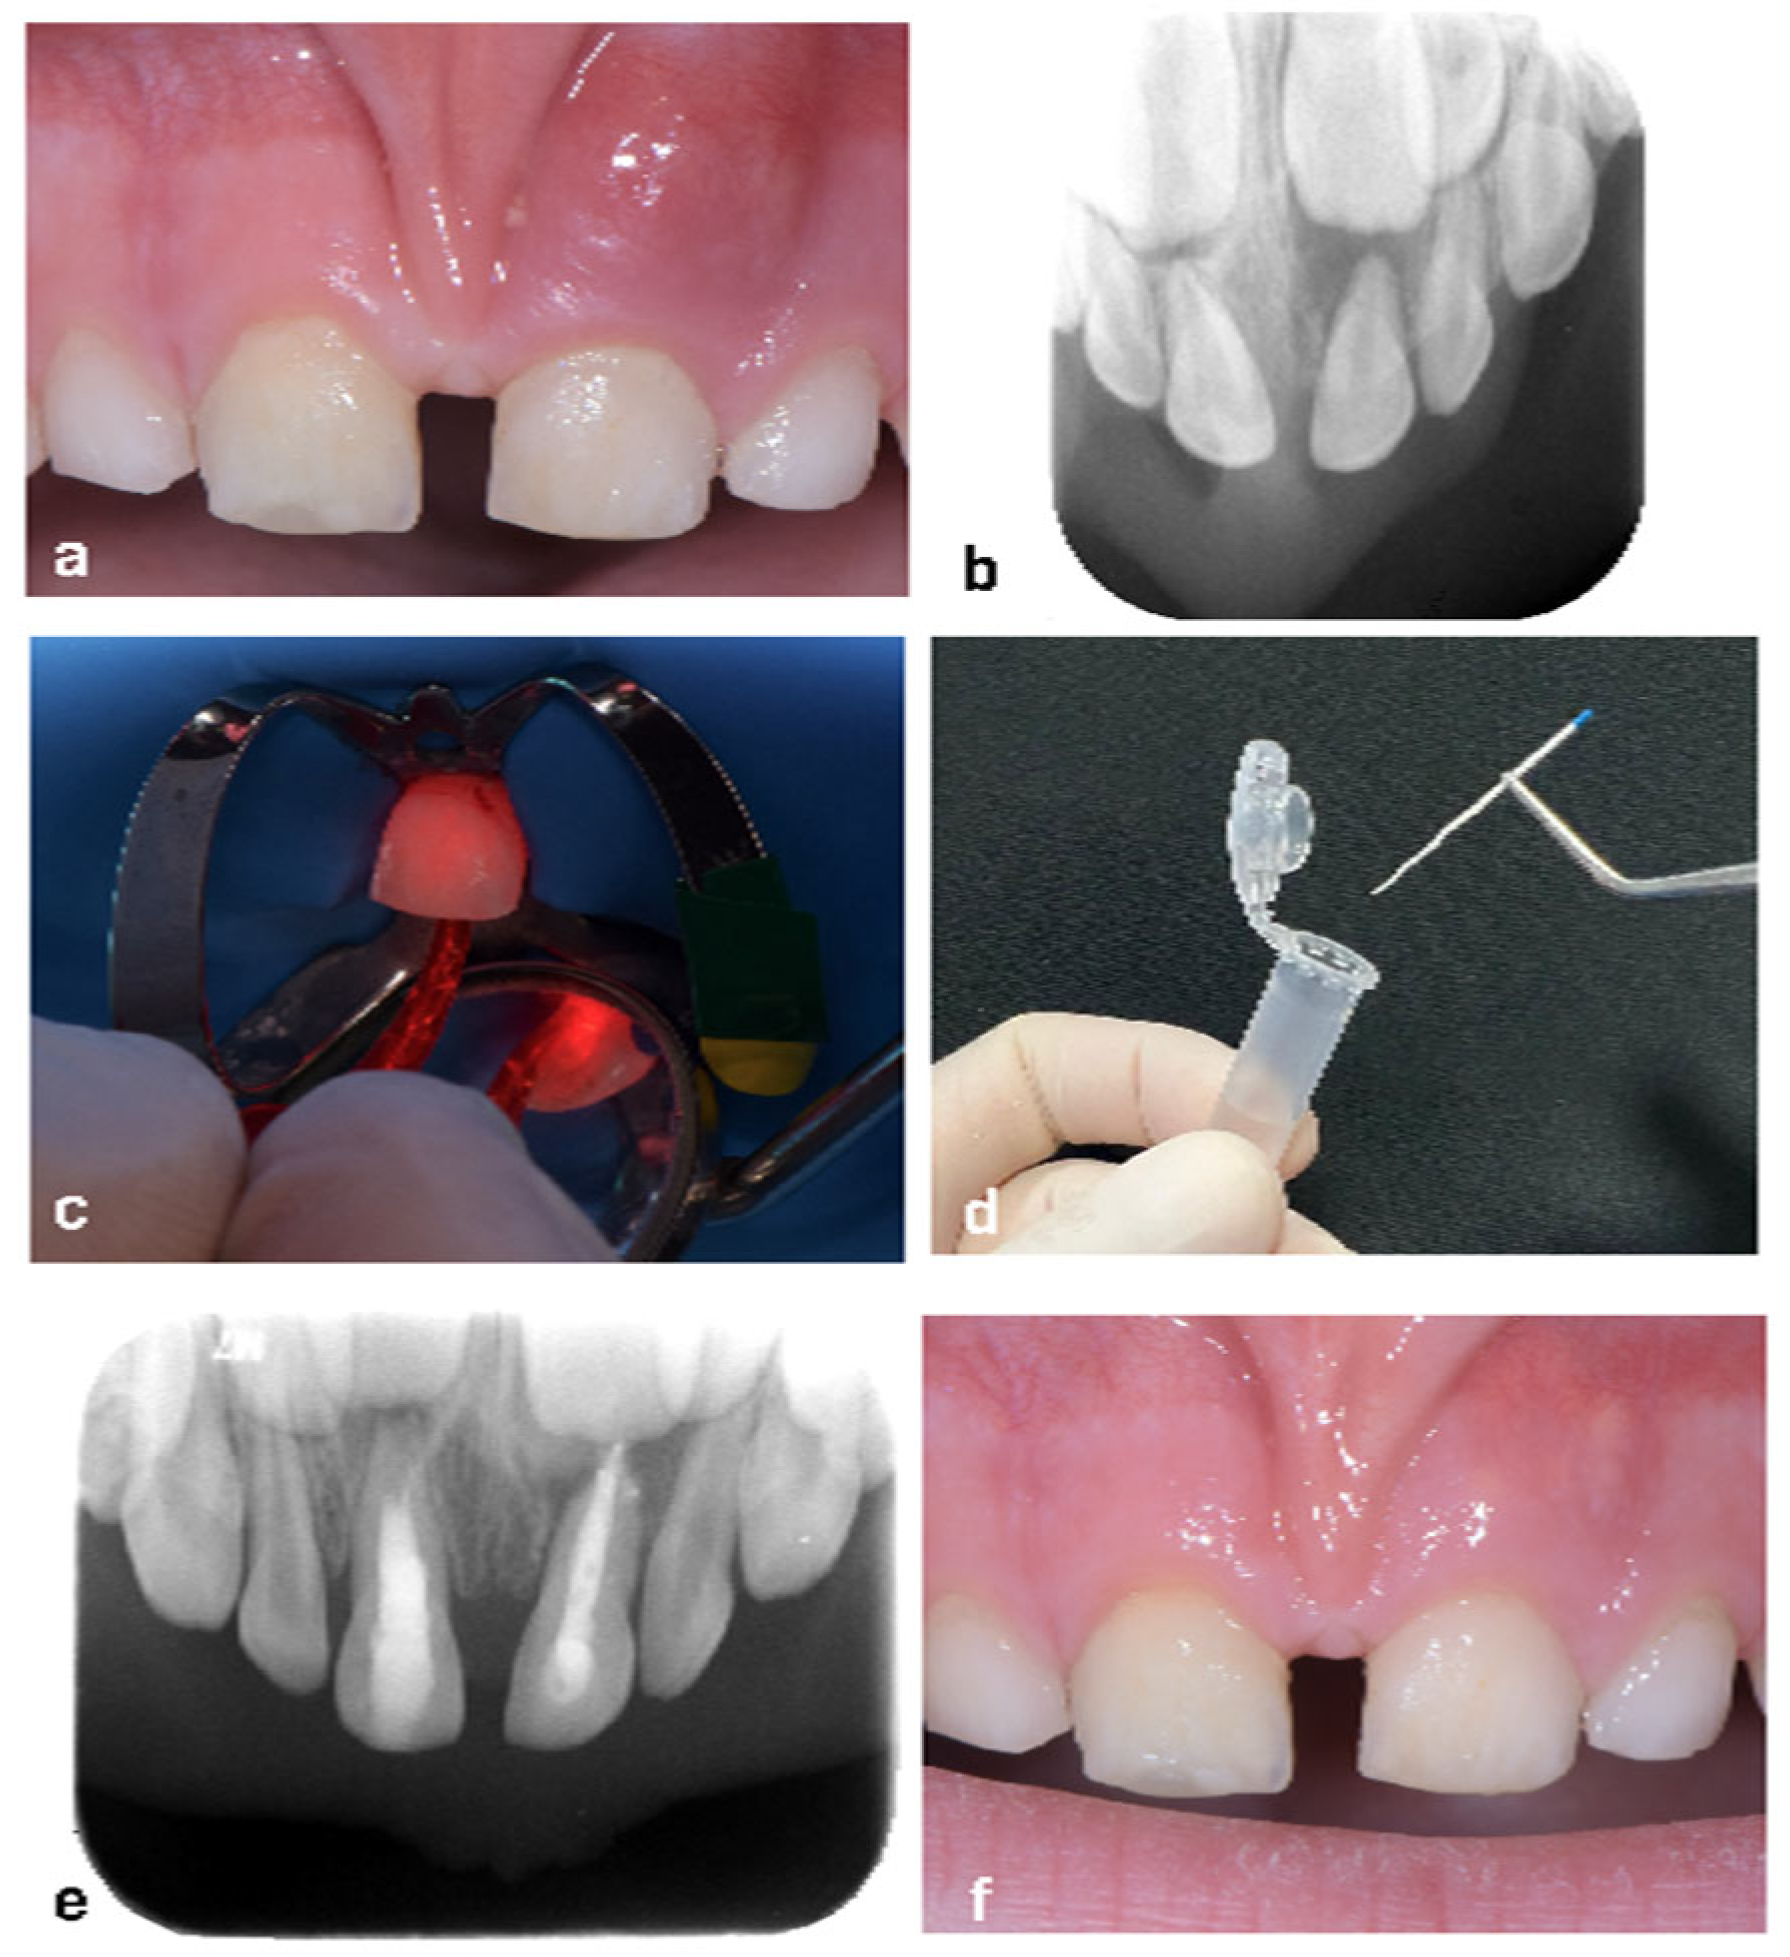

2.8. Case Report

- D’Ercole, S.; Carlesi, T.; Dotta, T.C.; Pierfelice, T.V.; D’Amico, E.; Tripodi, D.; Iezzi, G.; Piattelli, A.; Petrini, M. 5-Aminolevulinic Acid and Red Led in Endodontics: A Narrative Review and Case Report. Gels 2022, 8, 697. [Google Scholar] [CrossRef]